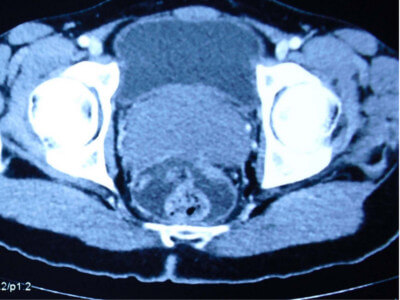

Mullerian cyst :

The mullerian duct cyst is a congenital condition represents remnant of the caudal ends of the fused müllerian duct, a structure that typically regresses in time. These cysts are typically located in the midline, behind the bladder, originating in the region urinary passage just below the level of prostate connected by a thin stalk. It is not associated with other congenital abnormalities of the urinary tract. The cystic fluid is devoid of sperms, and may be thick tenacious or sometimes blood stained. Rarely stones may occur within these cysts. It is common between 20 to 40 years.

The clinical presentation is varied, including urinary frequency, urgency, dysuria, urinary obstruction, hematuria, and pelvic pain. Digital rectal examination may reveal a midline mass superior to the prostate gland. Transrectal ultrasound and MRI will confirm the diagnosis.

These large cysts can be removed by laparoscopic surgery.